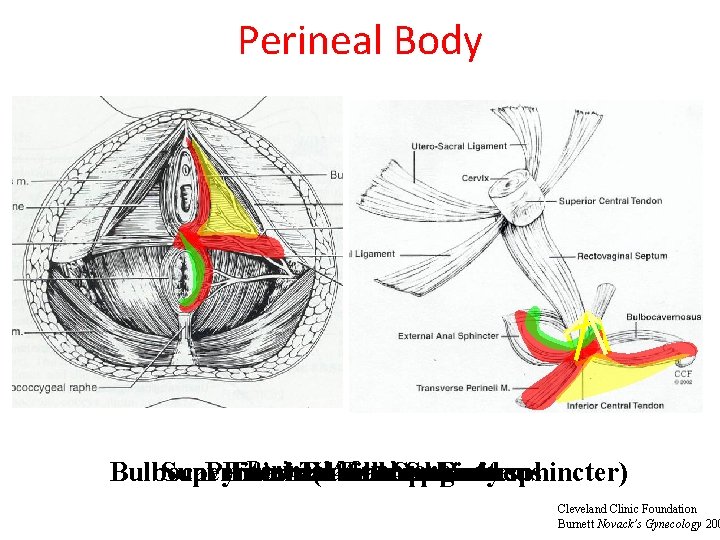

Perineal Body Perineal Membrane Superficial Pyramidal Internal External Transverse Anal Fibrous Anal. Sphincter Body perineus Bulbocavernosis (urethrovaginal sphincter) Cleveland Clinic Foundation Burnett Novack’s Gynecology 200